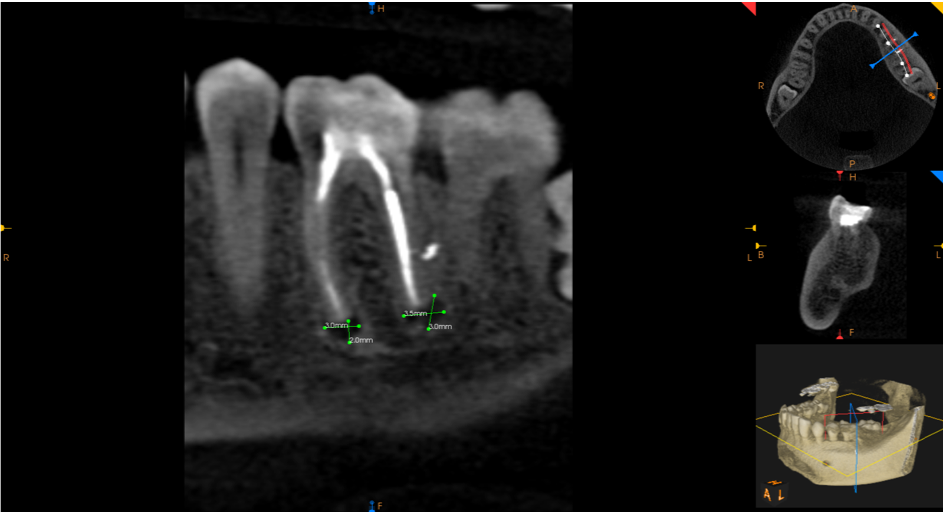

Ząb 36 – po leczeniu kanałowym. Wypełnione trzy kanały. Kanały dystalny i policzkowy wypełnione na całej swojej długości, w kanale językowym w części przywierzchołkowej materiał wypełniający niewidoczny (2mm). Wokół wierzchołków korzeni widoczne ogniska rozrzedzenia struktury kostnej o średnicy: korzeń mezialny – 2mm x 3mm, dystalny 3,5mm x 3mm.

Obecność uszczelniacza endodontycznego z boku korzenia oraz radiologiczne przejaśnienie widoczne w tym miejscu w tkankach korzenia dystalnego mogą sugerować uszkodzenie korzenia w tym obszarze.